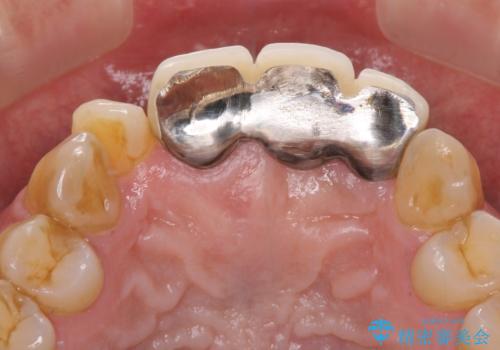

- 保険診療の前歯のブリッジが、形態も色も不自然で気になるとのことで来院された患者様です。

神経の抜かれている土台の歯は根管治療を行った上で、オールセラミックブリッジにより補綴することとしました。